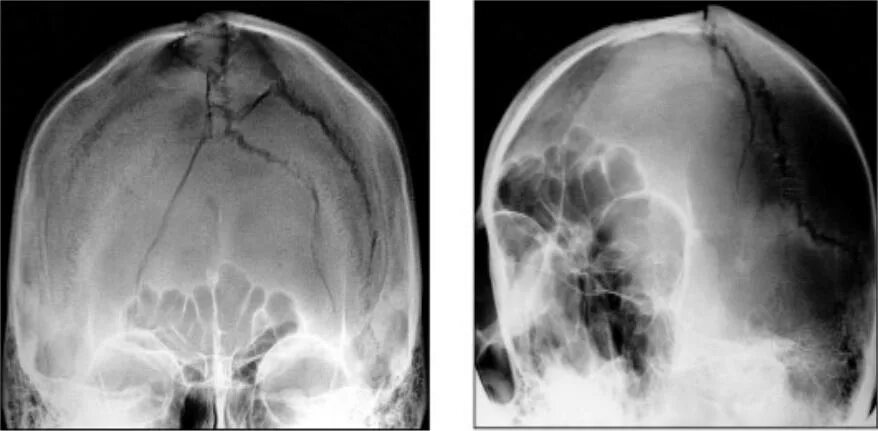

Оскольчатый перелом черепа